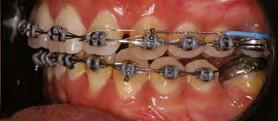

en paciente adulto tratado con extracciones de primeros molares permanentes. Reporte de caso

Dentista y Paciente 52 Sonriendo al futuro

Extraer los primeros molares permanentes puede ser una opción de tratamiento en ciertos casos de ortodoncia, como aquellos con apiñamiento moderado, biprotrusión, mordidas abiertas, o problemas de clase II y III que requieran extracciones. Además, se considera esta opción cuando los primeros molares están afectados por caries extensas u otras afecciones, lo que los hace más adecuados para la extracción y evita tratamientos restaurativos extensos o la necesidad de implantes en el futuro. Este artículo presenta el caso de una paciente en el que se optó por extraer los primeros molares superiores e inferiores para lograr resultados clínicos óptimos tanto en términos faciales como oclusales.

Palabras clave: extracción, primer molar, maloclusion, tratamiento ortodoncia.

Las extracciones dentales en los tratamientos de ortodoncia pueden ser indicadas en casos de caries extensas, restauraciones deficientes y/o extensas en premolares sanos, patologías periapicales, apiñamiento posterior y mordidas abiertas anteriores. La extracción de primeros molares permanentes es uno de los muchos planes de tratamiento en algunos casos de ortodoncia, en los cuales se presentan situaciones donde los primeros molares se encuentran comprometidos por lesiones cariosas extensas o alteraciones del desarrollo, por lo cual pueden ser candidatos para ser extraídos en casos donde se realizará tratamiento ortodóntico de pacientes como en los que se presentan apiñamiento moderado, biprotrusión, mordidas abiertas, clase II y III, casos en los cuales es necesario realizar exodoncias. Las extracciones posteriores producen una rotación antihoraria mandibular lo que podría ser conveniente en pacientes cuyas características faciales no se deben comprometer, como en pacientes con ángulo nasolabial obtuso, donde una significativa retracción de los dientes anteriores podría causar mayor apertura de este, lo que representaría en un resultado estético negativo y en camuflaje de pacientes clase II esqueléticas (extracciones superiores) y III (extracciones inferiores).1

189. Mayo 2024 53 Tratamiento ortodóncico

Cerrillo Lara Daniel. Ibarra Ramiro Jaime Tadeo. José de Jesús Anaya. Universidad Autónoma de Baja California. Campus Tijuana. Especialidad en Ortodoncia

Reporte del caso

Paciente del sexo femenino de 39 años de edad, sin datos patológicos aparentes, acude a la clínica de ortodoncia de la Facultad de Odontología campus Tijuana en diciembre del 2016. Su motivo de consulta fue: "Tengo el diente de abajo mal acomodado" En las fotografías extraorales se observa un paciente mesomorfo, biotipo mesoprosopo, línea superciliar asimétrica, línea bipupilar simétrica, nariz asimétrica, línea comisural asimétrica, labios medianos, tercio inferior aumentado respecto al medio y superior. Presenta perfil convexo, con un ángulo nasolabial obtuso (100°), surco mentolabial (122°). Línea dental superior desviada hacia la izquierda con respecto a línea media facial, muestra 100% de coronas dentales al sonreír. En el análisis intraoral se observa dentición permanente, líneas medias no coincidentes, microfracturas de OD #11 Y #21, clase molar indeterminada bilateralmente por ausencia de OD #16 Y #26, clase I canina bilateral, forma de arcada ovoide en superior, apiñamiento leve, #11, #12, #21 mesiorotados y #25 distorotado, forma de arcada ovoide en inferior, apiñamiento leve y OD #41 lingualizado, presencia de torus mandibular. Sobremordida horizontal de 2 mm y vertical de 20%. En el análisis radiográfico se muestran 26 dientes presentes en boca, ausencia de OD #16 y #26, presencia de #18, #28, #38 y #48 retenidos, altura de ramas mandibulares simétricas, densidad ósea

uniforme, relación corona-raíz 1:1; se observa además una maloclusión clase II esquelética, con crecimiento vertical, dientes anteroinferiores proinclinados así como los anterosuperiores.

Objetivos del tratamiento

Mejorar perfil del paciente, lograr clase molar I bilateralmente con mesialización de #37 y #47, después de extraer primeros molares mandibulares, mantener clase I canina bilateralmente, así como las sobremordidas vertical y horizontal, eliminar apiñamiento, corregir líneas medias, obtener oclusión funcional.

Plan de tratamiento interdisciplinario

Se remite al área de cirugía de la facultad de Odontología para extracciones de los OD #36 y #46 con el fin de armonizar la arcada inferior con la arcada superior, para después proceder a la mesialización de OD #37 y #47.

Plan de tratamiento ortodóncico

Se colocó aparatología fija superior e inferior tipo Alexander slot 0.022, se prosiguió a la alineación y nivelación, expansión superior e inferior con secuencias de arcos, mesialización de OD #37 y #47, recontorneo interproximal inferior, torque de raíces, armonización de arcadas, extracción de terceros molares inferiores y valoración de los superiores, retención removible superior e inferior.

Dentista y Paciente 54 Sonriendo al futuro

Figura 1. Fotografías extraorales de frente y de perfil. Figura 2. Fotografías intraorales iniciales.

Resultados

Se obtuvieron los resultados mencionados al inicio como clase I molar y canina, sobremordidas adecuadas, eliminación del apiñamiento, corrección de líneas medias y una oclusión funcional.

Discusión

La prevalencia de las extracciones dentales en los tratamientos de ortodoncia ha variado a lo largo de los años y esto es corroborado por 40 años de estudios retrospectivos llevados por Proffit, quien demuestra que durante los años 50 el porcentaje de

extracciones aumentó en un 10%, en los 60 en un 50 % y para los años 80 observó una reducción del 35%, al igual que para Peck y Peck que fue del 32% en ambos arcos.2-3

La extracción de algún diente siempre ha sido tema de discusión y aún más cuando son extracciones de primeros molares, ya que en un tratamiento por lo regular se considera que estos órganos dentarios son llaves fundamentales de la oclusión; sin embargo, Pérez en 2015 afirma que el tratamiento con extracciones de primeros molares tiene resultados positivos en el perfil, tal como

189. Mayo 2����2�� 55 Tratamiento ortodóncico

Figura 3. Modelos de estudio iniciales. Figura 4. Ortopantomografia inicial. Figura 5. Figura 6. Fase de alineación y nivelación.

sucedió en este caso y los reportados por Bahoquez en 2015. Rey en 2012 menciona también aquí resultados favorables al extraer los primeros 4 primeros molares a pesar de ser considerados piezas claves en la oclusión.4-5

Conclusión

La extracción de los primeros molares se presenta como una alternativa

efectiva para abordar casos de mordida abierta esquelética, perfiles convexos, rotación horaria de mandíbula entre otros, logrando resultados estables, funcionales y estéticamente satisfactorios. Es crucial destacar que esta decisión terapéutica requiere una cuidadosa elección de casos, así como una habilidad clínica y experiencia considerable para asegurar que las expectativas y resultados del tratamiento no se vean comprometidos.6

Dentista y Paciente 56 Sonriendo al futuro

Figura 7. Cierre de espacios superior e inferior. Figura 8. Retracción del segmento anterior. Figura 9. Fotografias intraorales finales.

Referencias

1. Rey D, Oberti G, Sierra A. Extraccion del primer molar permanente como una alternativa en el tratamiento de ortodoncia. Rev. CES Odont. 2012;25(1) 44-53.

2. Proffit WR. Forty-year review of extraction frequencies at a university orthodontic clinic. Angle Orthod. 1994;64(6):407–14.

3. Peck S, Peck H. Frequency of tooth extraction in orthodontic treatment. Am J Orthod. 1979 nov;76(5):491–6.

4. G. (2015). Tratamiento de mordida abierta con extracciones de primeros molares. Reporte de caso. Revista Mexicana de Ortodoncia, 3(4), 266–273.

5. Bahoquez, A. (2015). Exodoncias de primeros molares y verticalización de tercer molar inferior en paciente con mordida abierta, reporte de caso. Revista Latinoamericana de Ortodoncia y Odontopediatria.

6. Seddon JL. Extraction of four first molars: a case for a general practitioner? J Orthod. 2004 jun; 31(2):80-5.

7. Daugaard-Jensen I. Extraction of first molars in discrepancy cases. Am J Orthod. 1973 ago;64(2):115– 36.

8. Williams R. Single arch extraction--upper first molars or what to do when nonextraction treatment fails. Am J Orthod. 1979 oct;76(4):376–93.

189. Mayo 2����2�� 57 Tratamiento ortodóncico

Figura 10. Fotografias intraorales finales. Figura 11. Radiografía lateral de cráneo final. Figura 12. Fotografias extraorales finales.

Mucho cuidado con los equipos de rayos X intraorales portátiles

¿Está justificada esta advertencia?

Dentista y Paciente 58 Boletín

La redacción

En Dentista y Paciente queremos que los odontólogos conozcan el riesgo que implica el uso indebido de fuentes de radiación ionizante.

Los equipos portátiles están diseñados para llevar a cabo una exposición con el operador sujetando el equipo con ambas manos, y debido a la imposibilidad de alejarse del mismo a la distancia reglamentada, el operador se encontrará expuesto a una dosis de radiación ionizante once veces mayor, siendo esto el mejor de los casos.

Estamos conscientes de que la mayoría de los odontólogos ignoran los riesgos que implica el uso de fuentes de radiación, los cuales aumentan con la frecuencia y dosis de la misma, es por eso que nuestro deber nos llama a advertir al odontólogo para prevenir antes que lamentar.

En la literatura sobre la seguridad radiológica con equipos intraorales portátiles, hemos observado un creciente número de opiniones negativas sobre el uso de equipos diseñados para que el operador los sujete con sus manos para poder llevar a cabo así, una toma radiográfica periapical.

Esto implica que, de utilizarse el equipo portátil en el consultorio dental, el odontólogo tendrá en sus manos la fuente generadora de radiación, algo

189. Mayo 2024 59 Mucho cuidado con los equipos de rayos X intraorales portátiles

que no estaba previsto en la Norma Reguladora de Seguridad Radiológica NOM-229-SSA1-2002 (https:// www.gob.mx/cms/uploads/attachment/file/839898/IB_NOM229_ Infografia_24-03-2023_light.pdf), misma que excluyó de su campo de aplicación los equipos de rayos X convencionales, por considerar que los equipos de rayos X periapicales fijos tradicionales no presentarían mayores riesgos sanitarios al ser utilizados con los protocolos de seguridad sugeridos por ALARA, ICRP y otras instituciones, mismas que recomiendan mantener una distancia mínima de 2 metros entre el operador y la fuente generadora de rayos X, al efectuar el disparo mediante un disparador con cable retráctil, o con la opción de instalar un disparador remoto fuera del cuarto radiográfico.

Muchos odontólogos ignoran o subestiman los daños de tipo determinísticos o estocásticos, que son los causantes de provocar alteraciones cromosómicas a la célula, esto debido al uso indebido de fuentes

Muchos odontólogos ignoran o subestiman los daños de tipo determinísticos o estocásticos, que son los causantes de provocar alteraciones cromosómicas a la célula, esto debido al uso indebido de fuentes generadoras de radiación ionizante, pues aquellos que no lo saben suelen considerar al equipo portátil un avance tecnológico, cuando en realidad estos productos fueron diseñados para otras aplicaciones, al considerar que en sus países de origen su uso en el consultorio dental está restringido por normas de seguridad radiológica, debido a la imposibilidad para el operador de alejarse de la fuente de radiación, exponiéndose así a una dosis de radiación ionizante, por radiación dispersa y de fuga, mucho mayor de la que recibiría con un equipo fijo tradicional, al aplicar los protocolos antes mencionados.

Dentista y Paciente 60 Boletín

En la literatura sobre la seguridad radiológica con equipos intraorales portátiles, hemos observado un creciente número de opiniones negativas sobre el uso de equipos diseñados para que el operador los sujete con sus manos para poder llevar a cabo así, una toma radiográ����ca periapical��

1. RAGGI X IN MEDICINA-FISICA- TECNICA-APPLICAZIONI. Ed. GILARDONI S.p.A. 2.1.4.

2. ODOVTOS – Actualización en equipos de Rayos X portátiles en odontología. Lucía Barba Ramírez DDS, Deivi Cascante Sequeira DDS. Publicado en línea : 15-II-2021. Recuperado de: https://www.scielo.sa.cr/pdf/odovtos/v24n2/2215-3411-odovtos- 24-02-26.pdf

3. Revisión de las principales normas de protección radiológica para el uso de equipos de Rayos-X en odontología. Recuperado de: https://revistas.cientifica.edu.pe/index.php/ odontologica/article/download/538/6 19/